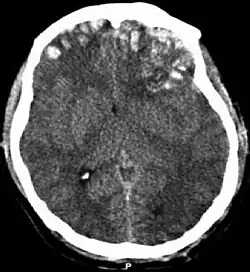

| CT scan showing cerebral contusions, hemorrhage within the hemispheres, subdural hematoma on the left, and skull fractures[1] | |